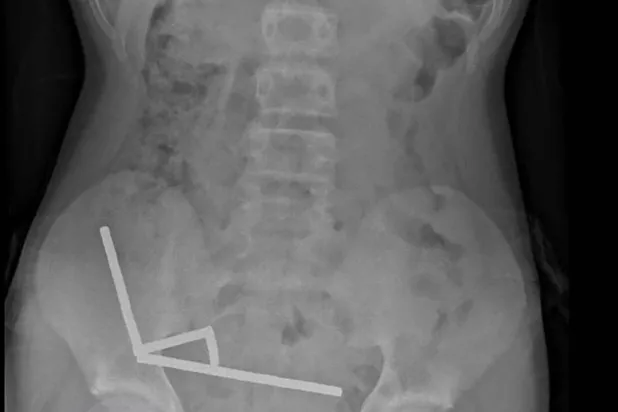

Varieties This undated handout released on October 24, 2025 from the New Zealand Medical Journal (NZMJ) shows an x-ray image of pieces of high-power magnets clumped up in the intestines of a New Zealand teenager in Tauranga. Handout / NEW ZEALAND MEDICAL JOURNAL (NZMDJ)/AFP

Surgeons Remove Up to 100 Magnets from N. Zealand Teen's Gut

A 13-year-old boy in New Zealand swallowed up to 100 high-power magnets he bought on Temu, forcing surgeons to remove tissue from his intestines, doctors said…